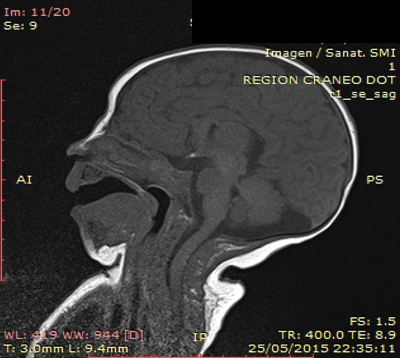

Agregó movimientos anormales y anisocoria. Se realiza carga de fenobarbital y RNM de cráneo urgente con enfoque de silla turca que informa: neurohipófisis ectópica asociada a tallo hipofisario y adenohipófisis hipoplásica. Hipoplasia del nervio óptico derecho e hipotrofia posterior del cuerpo calloso (Figura 1).

Figura 1: RNM de cráneo: neurohipófisis ectópica asociada a tallo hipofisario y adenohipófisis hipoplásica

En el caso presentado la impresión clínica fue de reiterados episodios de shock neonatal en los cuales se descartaron etiologías infecciosas, cardiovasculares y metabólicas. En el primer episodio de shock se utilizaron corticoides como parte del tratamiento sin realizarse los estudios correspondientes, lo que probablemente enmascaró y retrasó el planteo diagnóstico. Al realizar la RNM se constató una neurohipófisis ectópica, adenohipófisis hipoplásica e hipoplasia del nervio óptico, y con los estudios hormonales posteriores se realizó diagnóstico de insuficiencia suprarrenal secundaria e hipotiroidismo secundario. Por afectación del eje hormonal asociado a los hallazgos imagenológicos realizamos diagnóstico etiológico de disrupción del tallo hipofisario.

La RM es la técnica diagnóstica de elección para la valoración de eje hipotálamo-hipofisario e identificar anomalías estructurales asociadas. Dicha información morfológica es muy valiosa tanto para el diagnóstico inicial como para el seguimiento de pacientes con hipopituitarismo congénito6. Entre las múltiples variaciones se destacan: hipófisis anterior ausente o normal, lóbulo posterior de la hipófisis ectópico a nivel de la base del hipotálamo o a lo largo de todo el tallo hipofisario, aunque también puede estar ausente o normal, y forma del tallo hipofisario interrumpida, delgada, grande, ausente o normal7.